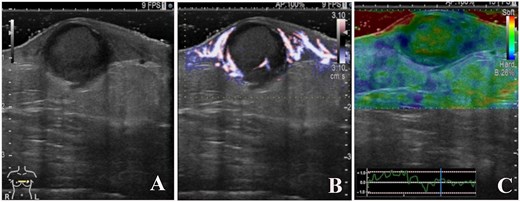

B-mode ultrasound imaging revealed that the nodule had an ill-defined, oval-shaped, and demonstrated dorsal acoustic amplification and lateral shadowing and heterogeneous pattern with a hypoechoic rim (A). Color doppler sonography showed blood flow signals mainly around the nodule (B), and on ultrasound elastography, the nodule appeared green-to-orange (C).

A 93-year-old woman presented to the outpatient breast clinic with a 2-day history of pain and redness in the left breast. She reported that she had not noticed a nodule in left breast previously. Physical examination revealed a soft-to-hard nodule of ~1 cm in diameter in the inner lower region of the left breast, accompanied by redness, blistering, and soreness of the surrounding skin (Fig. 1). Her body temperature was 36.5°C, and laboratory data and vital signs were unremarkable. Mammography revealed a focal asymmetric density of ~1 cm in diameter in the inner lower region of the left breast (Fig. 2A and B), and B-mode ultrasound imaging indicated that the nodule was mainly located in the subcutaneous fat layer along with dorsal acoustic amplification and lateral shadowing, and was characterized by a heterogeneous pattern with a hypoechoic rim that was ill-defined on the nipple side (Fig. 3A). In addition, color Doppler sonography showed blood flow signals primarily near the nodule (Fig. 3B), whereas the nodule appeared green-to-orange on ultrasound elastography (Fig. 3C). We used an ultrasound-guided VABD (Mammotome ® Elite ™) for pathological examination and to reduce inflammation. After local anesthesia, a 5-mm skin incision was made away from the inflamed skin on the nipple side of the lesion. Under ultrasound guidance, a 10-gauge operating needle was advanced through the incision (Fig. 4A) and positioned posterior to the lesion (Fig. 4B). The direction of the needle head aperture was adjusted to face the lesion in multiple directions. The lesion was excised toward the skin using a rotating blade with vacuum aspiration (Fig. 4C), and this maneuver was repeated without significantly affecting the overlying skin. The time from insertion to removal of operating needle was 5 min, and the obtained specimens were sent for bacterial culture and pathological examination. Upon completion of the procedure, a compression dressing with gauze was applied for 1 day. No further wound healing care was provided. Histological examination revealed that the lesion comprised mature stratified squamous epithelium and laminated layers of keratin, which was consistent with an EC (Fig. 4D). Examination of bacterial cultures at 9 days after the treatment revealed the presence of Prevotella bivia, Peptostreptococcus asaccharolytics, and Staphylococcus epidermidis. However, the inflammation had subsided before the bacterial examination report was obtained. Although the symptoms and inflammation disappeared within a week post-treatment, a red nodule of 4–5 mm in diameter persisted (Fig. 5A). Ultrasound images